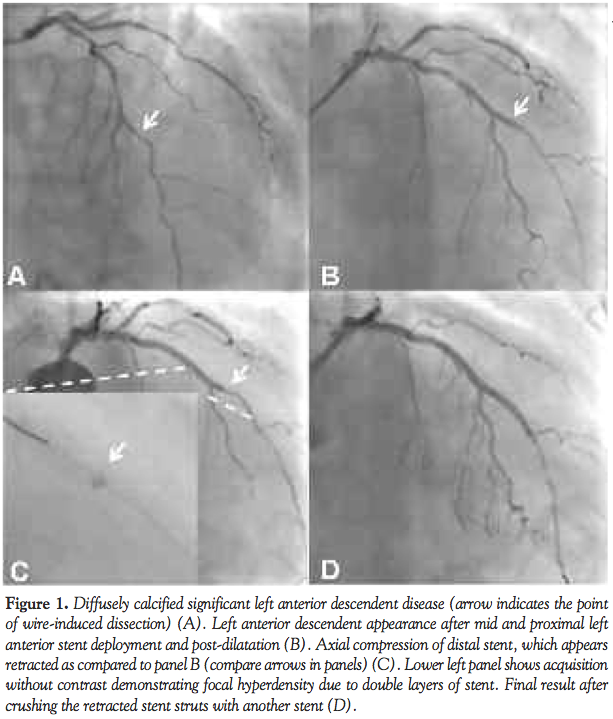

Case Report. An 81-year-old patient was referred for coronary angiography due to crescendo angina and anterior T-wave inversion on the ECG. Coronary angiography revealed proximal occlusion of a non-dominant right coronary artery, moderate ostial circumflex lesion, and diffusely calcified significant left anterior descendent (LAD) disease (Figure 1A). Fractional flow reserve on the ostial circumflex lesion was 0.83, so that percutaneous coronary intervention of LAD was planned. Percutaneous coronary intervention was initially complicated by a wire-induced dissection distal to the third septal branch (Figure 1A, arrow). Multiple pre-dilations with 1.5 and 2.0 balloons were followed by successful deployment of a 2.25 mm x 20 mm drug-eluting stent (Promus Element, Boston Scientific) to mid LAD, which was extended proximally with a similar 2.5 mm x 28 mm stent. Both stents were then successfully post-dilated with a 2.5 non-compliant balloon. As the distal dissection was not completely covered (Figure 1B), we intended to implant a further stent distally. An attempt to pass a BMW Universal (Abbott Vascular) as a “buddy” wire was unsuccessful and the wire was withdrawn with a gentle sensation of some traction. Thereafter, a change in the appearance of distal stent was obvious, with marked axial shortening and the concomitant reappearance of distal vessel dissection (Figure 1C). Attempts to advance 2.0, 1.5, and 1.1 balloons and a Corsair catheter (Asahi Intecc) over the original wire failed. A new wire had to be passed laterally through the deformed stent struts allowing fenestration with 1.1 and 2.0 balloons. The retracted portion of the stent was then finally “crushed” with 2.25 mm x 20 mm drug-eluting stent with a good angiographic result (Figure 1D).

Discussion. Axial stent deformation or longitudinal compression has been very recently described as the mechanical consequence of either guide catheter or IVUS imaging.1,2 Recognition of the potential for this complication is important and it requires the operator to be particularly careful to ensure axial alignment prior to passage of balloons/devices through recently deployed stents. In the present case it is likely that distal stent struts were disrupted during placement of a buddy wire. The situation was probably aggravated by the presence of a distal dissection with possible vessel wall hematoma, which re-expanded once the distal struts were crushed and deformed. As the stent lumen was completely obstructed, rewiring was only possible between stent struts with crushing of the distal retracted portion of the stent. This achieved a reasonable result, although full stent coverage of the dissection was not possible.